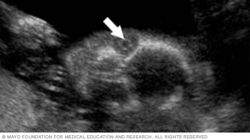

Below is an image of the base of the brain, called the cerebellum. This type of image usually is taken during an ultrasound done between 18 and 22 weeks of pregnancy.

The cerebellum is the part of the brain that controls muscle coordination and balance. Checking its shape on an ultrasound can help the health care team find neural tube defects. The neural tube forms in the first few weeks of pregnancy. The top of the tube becomes the brain. The rest of it becomes the spinal cord. Problems in neural tube development may lead to conditions such as spina bifida, in which part of the neural tube doesn't develop or close correctly. This can lead to problems in the spinal cord and in the bones of the spine.